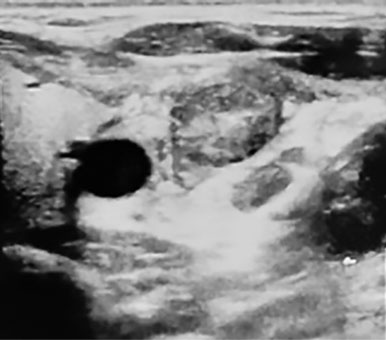

Проведено ультразвуковое исследование (УЗИ) сосудов шеи: в просвете левой яремной вены визуализированы гиперэхогенные тромботические массы (рис. 1, 2).

Рис. 1. Ультразвуковое исследование левой внутренней яремной вены (поперечный срез). Визуализируются тромботические массы

Рис. 2. Ультразвуковое исследование левой внутренней яремной вены (продольный срез). Визуализируются тромботические массы